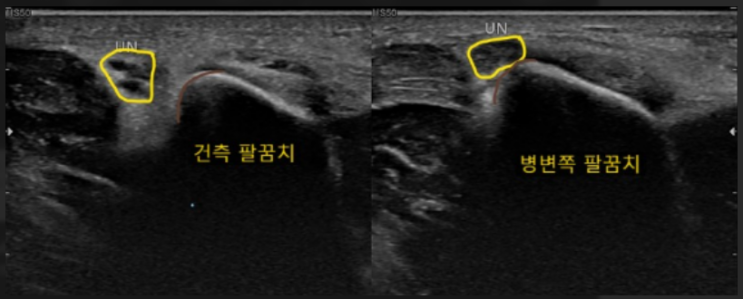

[팔꿈치] 척골신경 (아)탈구 dislocation of ulnar nerve

[4842] cubital tunnel & triceps snapping syn으로 UN 아탈구 초음파 Dynamic으로 확인되었고 cubi...